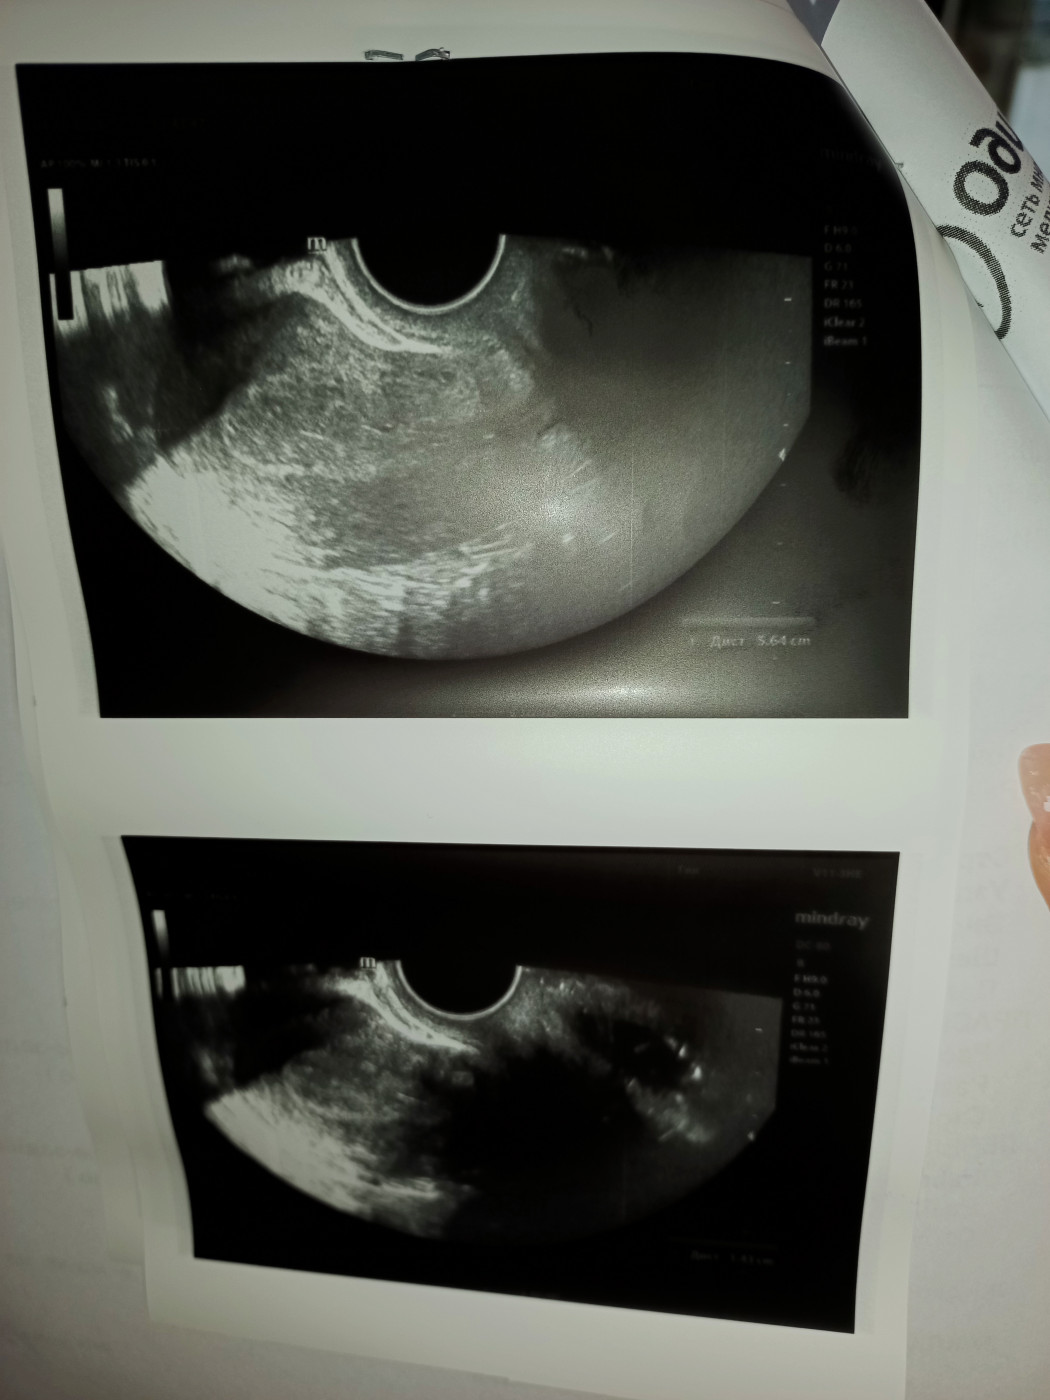

Результаты УЗИ

Киста, странные результаты повторного УЗИ